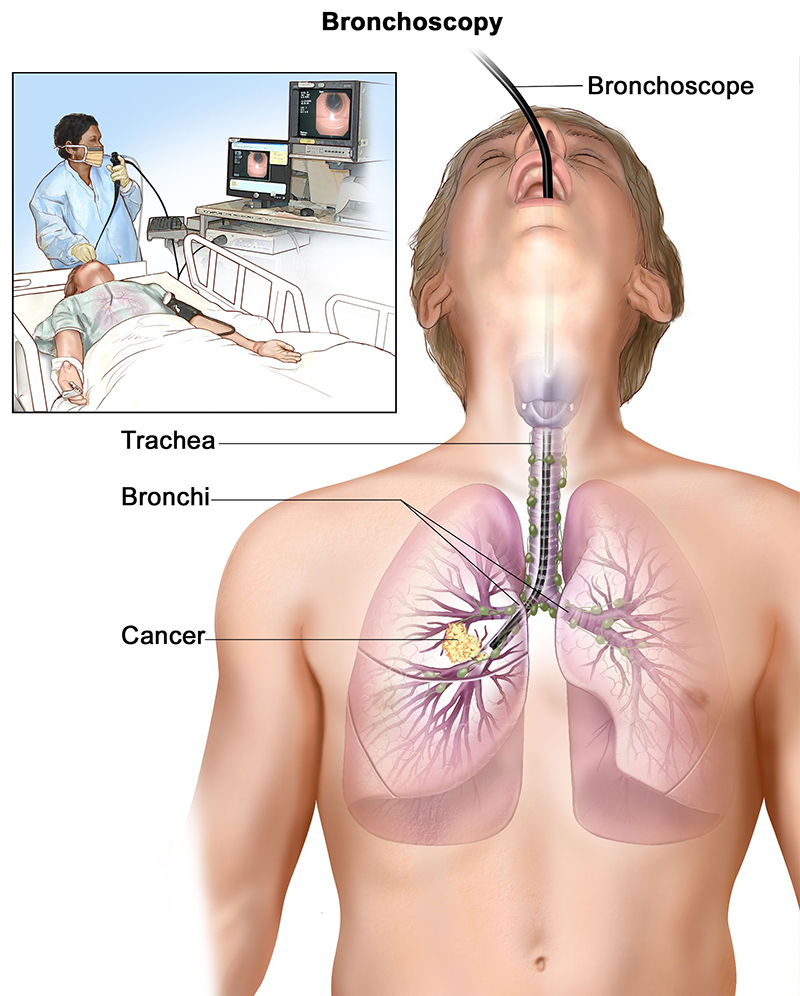

Bronchoscopy

Bronchoscopy is a medical procedure used to examine the inside of the airways and lungs using a thin, flexible tube called a bronchoscope. The bronchoscope is equipped with a light and camera, allowing doctors to view the trachea, bronchi, and smaller airways in real time. This procedure is essential for diagnosing and treating various respiratory conditions.

Bronchoscopy can be performed for several reasons, including investigating unexplained coughing, persistent lung infections, abnormal chest X-rays or CT scans, lung tumors, or bleeding. It also helps obtain tissue samples (biopsies), remove foreign objects, or clear mucus plugs that obstruct airflow.

There are two main types of bronchoscopy:

- Flexible Bronchoscopy: The most common method, where a flexible tube is inserted through the nose or mouth into the lungs. It is usually performed under local anesthesia and mild sedation, making it safe and well-tolerated.

- Rigid Bronchoscopy: This uses a rigid metal tube and is typically done under general anesthesia. It is used for more complex procedures like removing large obstructions or controlling heavy bleeding.